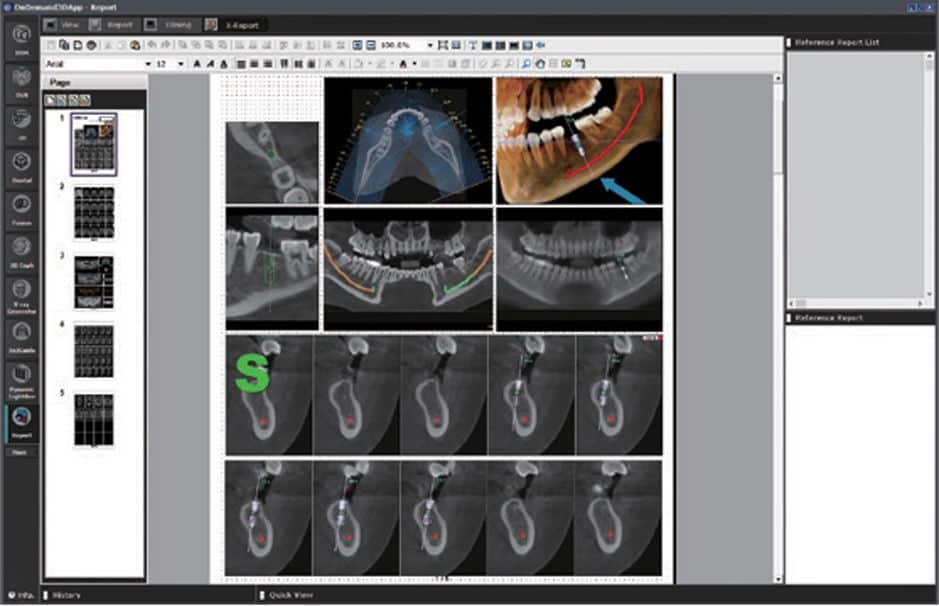

Report

Modulul Report este destinat utilizatorilor care doresc sa creeze rapid un raport simplu. Cu doar cateva click-uri se pot captura toate imaginile posibile care apoi pot fi integrate intr-un sablon de raport simplu. Acesta poate fi tiparit, arhivat sau exportat in format HTML. In plus, suporta imprimarea DICOM pentru a controla setul de imagini cu laser DICOM care creeaza imaginile clasice CT pe film.

Functionalitati: Capturare de imagini si crearea rapida de rapoarte simple. Export format HTML.

X-Report

Modulul X-Report este o optiune mai avansata pentru utilizatorii care doresc sa creeze sabloane de rapoarte personalizate pentru nevoile lor de raportare. Utilizand o functie inteligenta de inserare a imaginii, „Drag and Drop”, care poate fi setata la True Size sau la un nivel de zoom preferat, impreună cu mai multe optiuni de afisare. Permite crearea foarte rapida de sabloane adaptate pentru chirurgie, cu datele si imaginile fiecarui pacient. Rapoartele pot fi tiparite sau exportate ca format HTML, PDF, PPT, JPG.

Functionalitati: Creare de template-uri pentru rapoarte personalizate ce rezulta in cresterea eficientei.